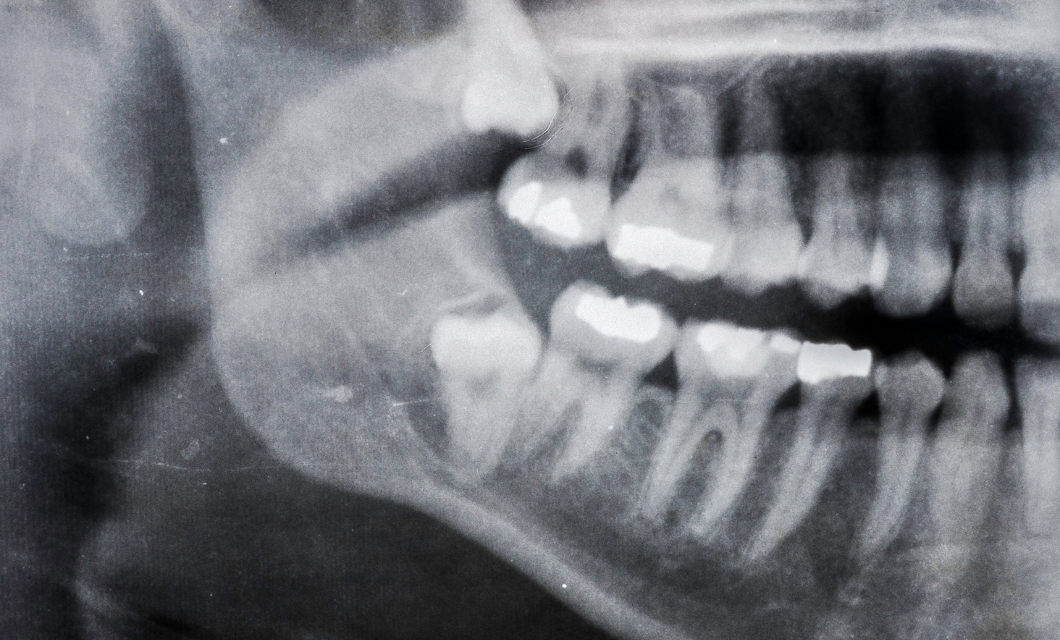

Impaction occurs when a tooth gets blocked by surrounding bone, gum tissue, or nearby teeth, preventing it from fully erupting into its proper position. This impaction can appear in a variety of ways, depending on the angle and position of the impacted tooth. Let's briefly evaluate different types of wisdom teeth impaction

Typically, wisdom teeth become visible between the ages of 17 - 25, and are the last teeth to come in. Your dentist will see your wisdom teeth on a dental x-ray. Impacted wisdom teeth do not always cause symptoms; however, your dentist will likely recommend wisdom teeth removal before complications occur. If you experience infection, damage to surrounding teeth, or other problems, you may suffer from:

You can deal with impacted wisdom teeth proactively by recognizing these symptoms and consulting with your dentist. Your dentist will conduct a complete examination, including X-rays, to examine the location and condition of your wisdom teeth and offer appropriate treatment choices, such as wisdom tooth extraction if necessary.